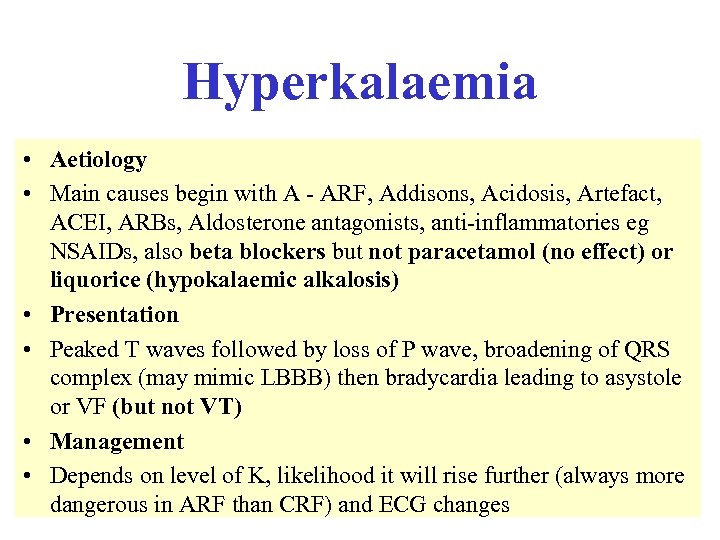

Hyperkalaemia • Aetiology • Main causes begin with A - ARF, Addisons, Acidosis, Artefact, ACEI, ARBs, Aldosterone antagonists, anti-inflammatories eg NSAIDs, also beta blockers but not paracetamol (no effect) or liquorice (hypokalaemic alkalosis) • Presentation • Peaked T waves followed by loss of P wave, broadening of QRS complex (may mimic LBBB) then bradycardia leading to asystole or VF (but not VT) • Management • Depends on level of K, likelihood it will rise further (always more dangerous in ARF than CRF) and ECG changes

Hyperkalaemia • Aetiology • Main causes begin with A - ARF, Addisons, Acidosis, Artefact, ACEI, ARBs, Aldosterone antagonists, anti-inflammatories eg NSAIDs, also beta blockers but not paracetamol (no effect) or liquorice (hypokalaemic alkalosis) • Presentation • Peaked T waves followed by loss of P wave, broadening of QRS complex (may mimic LBBB) then bradycardia leading to asystole or VF (but not VT) • Management • Depends on level of K, likelihood it will rise further (always more dangerous in ARF than CRF) and ECG changes